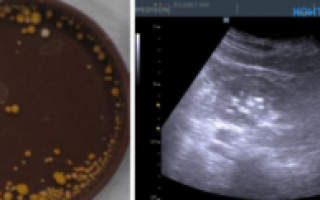

- Ультразвукового исследования – определение микролитиаза (выявление маленьких камней различной структуры).

- УЗИ;

УЗИ почек и мочевого пузыря показывает наличие камней в лоханках, в мочеточниках.

К сожалению, оксалатные камни менее 6 мм размером чрезвычайно плохо визуализируются по УЗИ, поэтому даже при «чистой» ультразвуковой картине, но при наличии характерных отклонений в моче рекомендуется выполнение рентгенографии (урографии).